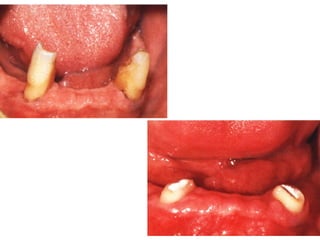

Indications for Overdentures

Few remaining teeth are present, not suitable for fixed or RPD

Mobile teeth: Reduction of unhealthy remaining periodontal

teeth, decrease the C/R ratio, inturn decrease the

hypermobility of teeth.

Severe attrition

Abnormal jaws

Congenital defects

Alternative treatment to single

dentures